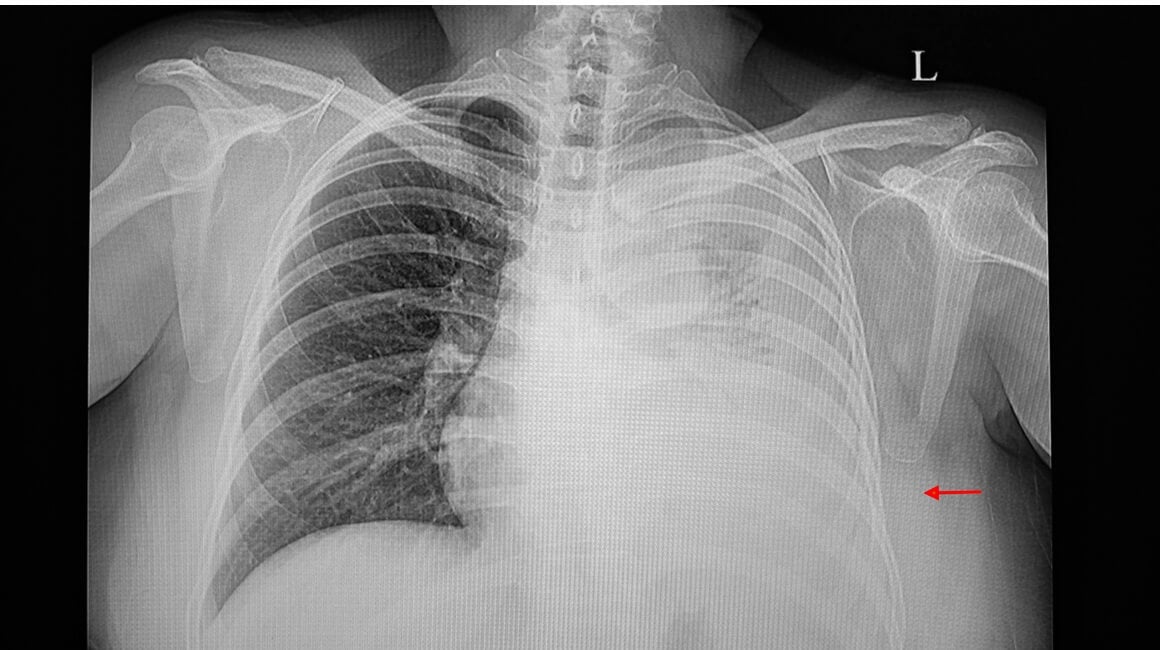

- pregled pluća X-zrakama, odnosno rendgen pluća – može učinkovito dokazati prisutnost tekućine u pleuralnom prostoru koja se pojavljuje kao bjelkasta mrlja u dnu pluća

Pleuralni izljev pluća može biti lokaliziran samo na jednu stranu, pa razlikujemo pleuralni izljev desno i pleuralni izljev lijevo, dok se pleuralni izljev kod djece javlja puno rjeđe.